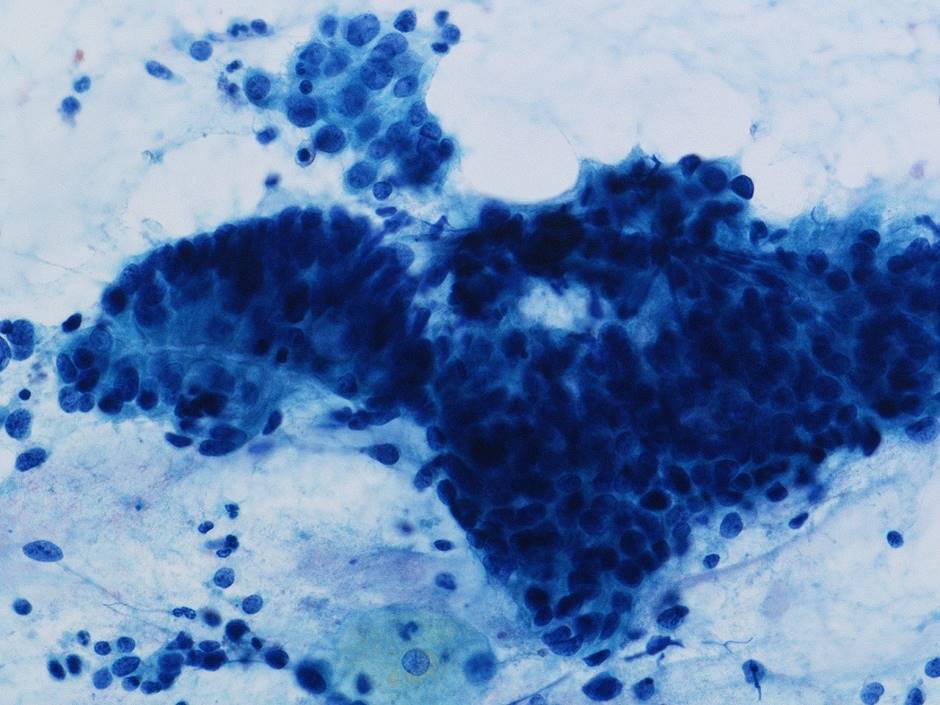

細胞診所見

背景に壊死物質は認められなかった。その中に偏在性核で核クロマチン増量を示す腺系異型細胞の不整形集塊を認めた。柵状配列や腺管構造もみられ上皮内腺癌を疑う細胞と考えた。またN/C比が高く細顆粒状の核クロマチンを有する傍基底型核異常を疑う細胞もみられた